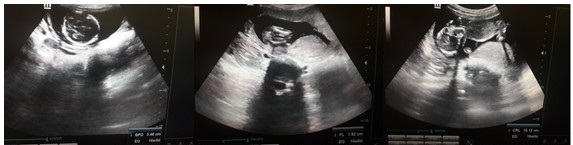

Se presenta el caso de una paciente de 26 años de edad, con historia obstétrica de gesta 3 partos 1 (eutócico), abortos 1 (provocado); con el antecedente de complicación obstétrica hemorrágica en embarazo anterior, por lo cual requirió tratamiento quirúrgico conservador. Con un periodo intergenésico de dos años, acudió a los servicios obstétricos con síntomas y signos de embarazo, amenorrea de aproximadamente 16 semanas, y sensación de pesadez en bajo vientre. Al examen físico se constató un aumento de volumen en hipogastrio, que podía corresponderse con una altura uterina de aproximadamente 15 centímetros; mediante el tacto vaginal se confirmó útero grávido de aproximadamente 16 semanas de gestación; y la ecografía obstétrica confirmó feto único, con latidos cardiacos presentes, placenta y líquido amniótico normal, así como mensuraciones fetales que correspondían aproximadamente con dicho tiempo de gestación. (Figura 1).